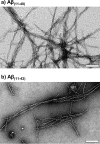

Alzheimer disease coincides with the formation of extracellular amyloid plaques composed of the amyloid-β (Aβ) peptide. Aβ is typically 40 residues long (Aβ(1-40)) but can have variable C and N termini. Naturally occurring N-terminally truncated Aβ(11-40/42) is found in the cerebrospinal fluid and has a similar abundance to Aβ(1-42), constituting one-fifth of the plaque load. Based on its specific N-terminal sequence we hypothesized that truncated Aβ(11-40/42) would have an elevated affinity for Cu(2+). Various spectroscopic techniques, complemented with transmission electron microscopy, were used to determine the properties of the Cu(2+)-Aβ(11-40/42) interaction and how Cu(2+) influences amyloid fiber formation. We show that Cu(2+)-Aβ(11-40) forms a tetragonal complex with a 34 ± 5 fm dissociation constant at pH 7.4. This affinity is 3 orders of magnitude tighter than Cu(2+) binding to Aβ(1-40/42) and more than an order of magnitude tighter than that of serum albumin, the extracellular Cu(2+) transport protein. Furthermore, Aβ(11-40/42) forms fibers twice as fast as Aβ(1-40) with a very different morphology, forming bundles of very short amyloid rods. Substoichiometric Cu(2+) drastically perturbs Aβ(11-40/42) assembly, stabilizing much longer fibers. The very tight fm affinity of Cu(2+) for Aβ(11-40/42) explains the high levels of Cu(2+) observed in Alzheimer disease plaques.